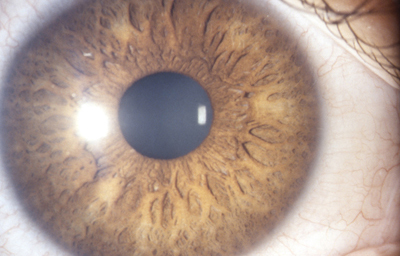

En la cara Anterior esta el pigmento que le da el color al Iris y dependiendo del grado de reabsorción u atrofia de esa capa anterior se pueden observar:

Las Criptas de Fuchs: que son pequeñas aberturas alrededor del collarete, producto de la atrofia o reabsorción de la hoja anterior del iris, que le permiten al estroma y a los tejidos mas profundos estar en contacto con el humor acuoso.

Cuando el Iris no tiene criptas, se considera que la reabsorción u atrofia de la hoja anterior (memb. pupilar) se detuvo en el circulo menor.

En la cara Posterior se ven pliegues radiales muy finos que se extienden desde el margen pupilar hasta el collarete ( miden ± 1.0 mm), y son conocidos como Pliegues radiales de contracción de Schwalbe. Existen ademas los llamados Pliegues estructurales de Schwalbe que son mas gruesos y mas distanciados en la porción ciliar de la cara posterior

El Color del Iris

El Iris en general es muy pigmentado con colores que comúnmente van del marrón, avellana, gris, verde y azul. Existen los iris sin pigmento en el Albinismo oculo-cutáneo en cuyo caso se ven blanco/rosados.

El color del Iris es un fenómeno complejo por efectos combinados por la textura, la pigmentación y el tejido fibrovascular del estroma, junto con la constitución epigenética del individuo. Desde el punto de vista óptico, la simple absorción o reflexión selectiva por algunas moléculas, como la hemoglobina o el colágeno del estroma que son componentes no pigmentados, puede tener influencia en el color que es observado.

A pesar de la gran variedad en el color del Iris, el único pigmento que contribuye en forma sustancial es la melanina; su cantidad, es uno de los factores que determina el color del iris en una persona. Estructuralmente el color depende de la cantidad variable de eumelanina (melaninas marron/negra) y pheomelanina (melaninas rojo/amarillo) producidas por los melanocitos derivados de la Cresta Neural. El grado de dispersión de la melanina que yace en racimos subcelulares en los melanosomas, tiene cierta influencia en el color que se observa, pero el grado de dispersión no es reversible ya que los melanosomas no son moviles.

En el recién nacido el Iris es de color gris azulado por falta de migración del pigmento, el color definitivo se muestra alrededor de los 6 meses de edad.